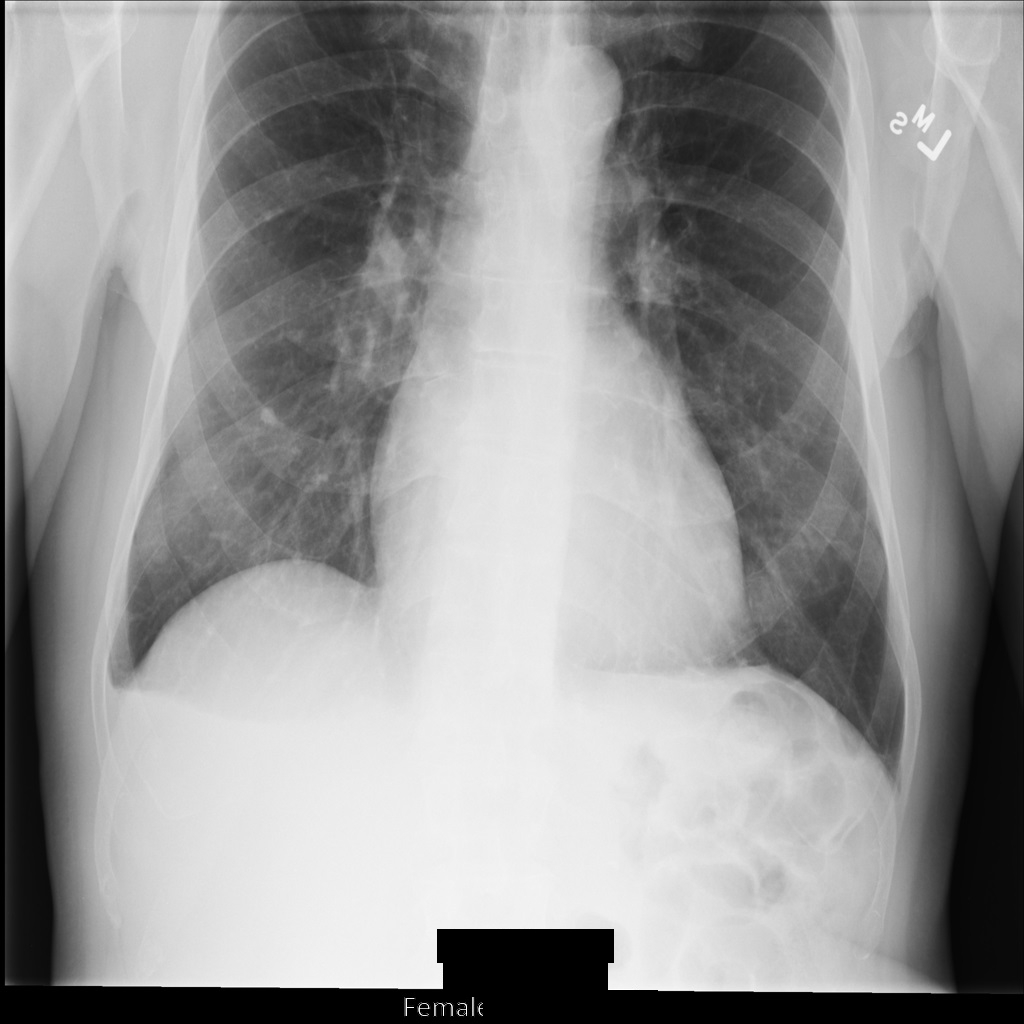

Après avoir anonymisé l'image à l'aide de REDACT_SENSITIVE_TEXT_CLEAN_DESCRIPTORS, elle se présente comme suit. Notez que tout le texte incrusté en bas de l'image n'a pas été masqué. Le texte Female s'affiche toujours, car PatientSex (0010,0040) ne fait pas partie des infoTypes DICOM par défaut.

REDACT_SENSITIVE_TEXT_CLEAN_DESCRIPTORS.Anonymiser des tags DICOM